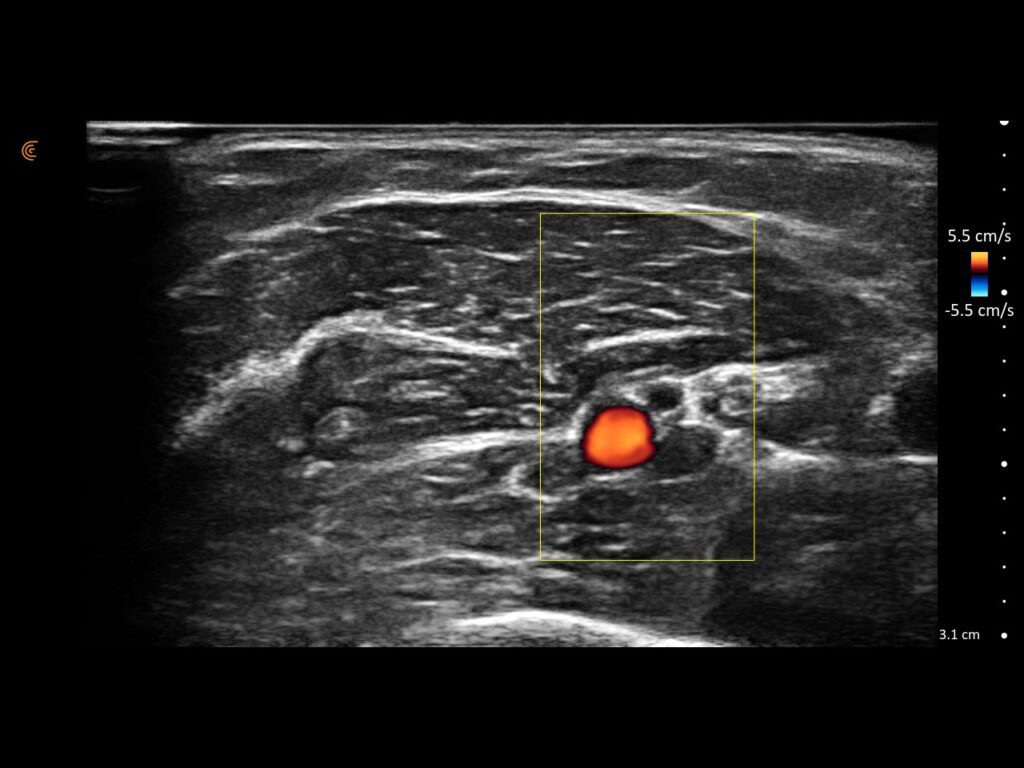

See Inflammation in Real Time.

Assess synovitis, enthesitis, and monitor treatment efficacy with high-resolution ultrasound, enabling precise, real-time joint and soft tissue evaluation, accurate needle guidance, and improved confidence in clinical decision-making.